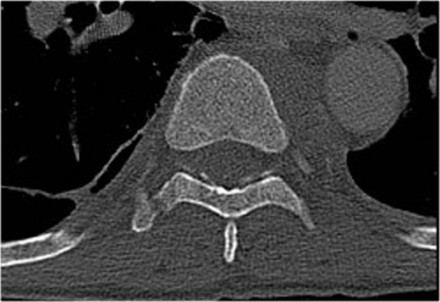

Sternum fracture

The image shows a vertebral fracture with a transverse fracture of the spinous process, but also a fracture of the sternum.

Analogous to the 3-column classification of Denis, some investigators

consider the sternum as the fourth column in upper thoracic spinal

fractures and recognize it as an independent variable in the assessment

and treatment of these patients (5).